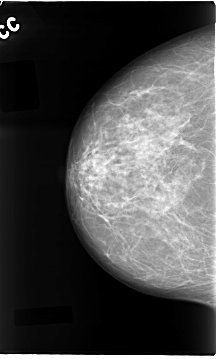

C_0087_1.LEFT_CC

LEFT_CC LINES 4696 PIXELS_PER_LINE 2704 BITS_PER_PIXEL 12 RESOLUTION 50 OVERLAY

FILE: C_0087_1.LEFT_CC.OVERLAY

TOTAL_ABNORMALITIES 2

ABNORMALITY 1

LESION_TYPE CALCIFICATION TYPE PLEOMORPHIC DISTRIBUTION CLUSTERED

ASSESSMENT 5

SUBTLETY 5

PATHOLOGY MALIGNANT

TOTAL_OUTLINES 1

ABNORMALITY 2